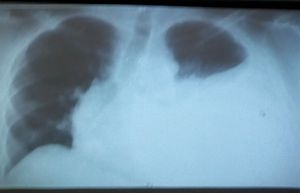

What do you think this rx is?

pneumothorax